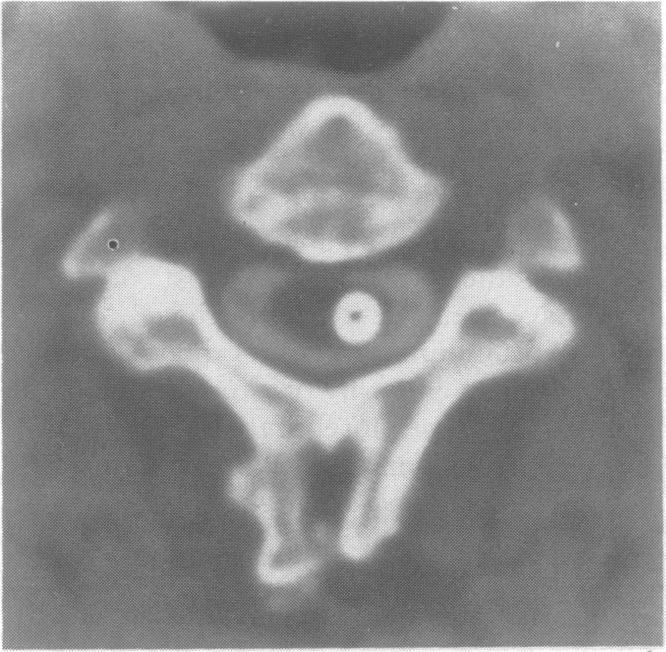

Spontaneous intraneural haematoma of the optic nerve.

J Neurol Neurosurg Psychiatry. 1991 Jul;54(7):653-4. doi: 10.1136/jnnp.54.7.653-a.